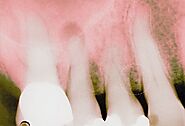

The next stage of gum disease is periodontitis, or gum infection. Increased inflammation causes the gums to recede, forming pockets between the teeth and gums. These pockets trap tartar, plaque, and food debris that eventually lead to infection and abscesses. Advanced gum disease damages the bone that supports teeth and is one of the leading causes of tooth loss in adults. See your dentist to treat receding gums.

https://www.umbrellamd.com/e-visit